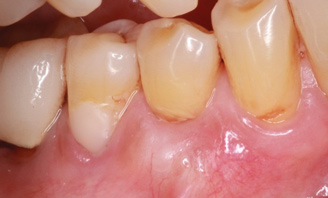

Fig 1. Miller Class I recession on tooth No. 11 (Fig 1) treated with tuberosity CTG (Fig 2). Note this CTG (which is the tuberosity CTG from Fig 5) was placed before the practitioner developed thinning techniques, so a keloid-like appearance was observed even 1 year after grafting.

Figure 1

A complication in using CT from the tuberosity reported in the literature is a tendency for clinicians to harvest tissue that is too thick.12 This can result in a keloid-like appearance similar to what may occur with an EPG. This excess thickness can be unesthetic (Figure 1 and Figure 2) and subsequently require a gingivoplasty to remove the superfluous tissue.12 This problem may perhaps be alleviated with proper thinning of the graft prior to insertion into the recipient area.

Regarding the avoidance of a gingivoplasty procedure later, there appears to be nothing in the literature describing the ideal thickness of a tuberosity CTG. From palatal and allograft thickness recommendations, one could hypothesize that the thickness be between 0.75 mm and 2 mm. This article will propose a graft thickness between 1 mm to 1.5 mm (Figure 3 and Figure 4) for the optimal functional and esthetic outcome and will discuss various procurement and fileting techniques.